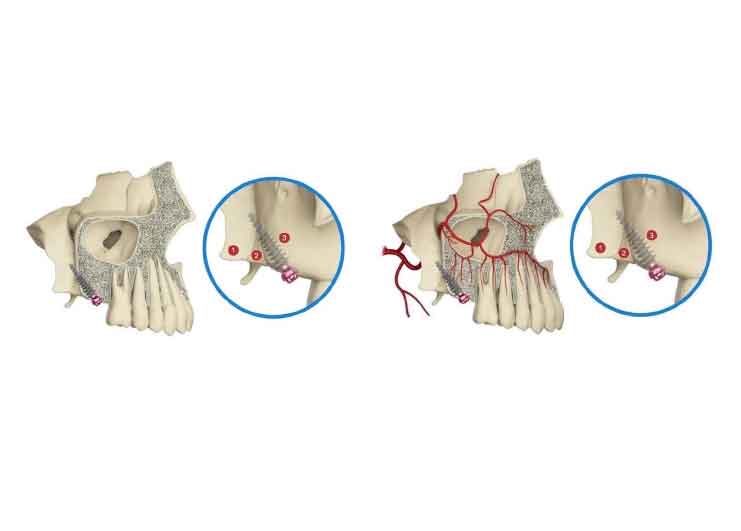

ザイゴマインプラント

上あごの骨が十分にない場合には、強固な頬骨に長めのインプラントを埋め込むことで、しっかりとインプラントを固定することができます。

脂肪組織をインプラント表面に挿入

血液循環を良くして、筋肉の可動域を広げます。